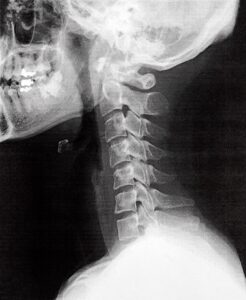

人の首の骨(頚椎)は本来、ゆるやかなカーブを描いて頭を支えています。

このカーブは「頚椎前弯」と呼ばれ、頭の重みを分散し、筋肉や神経に余計な負担がかからないようにする自然な構造です。

しかし、長時間のスマートフォン操作やデスクワークで前かがみの姿勢が続くと、首のカーブが失われ、まっすぐに近い状態になります。

この状態が「ストレートネック」です。